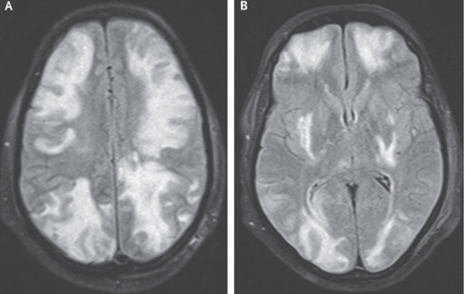

頭部MRI施行。T2強調像にて半球分水界パターンで皮質および皮質下の白質に高信号が示された。

以上より血管原性浮腫と一致するパターンと判断し、シクロスポリン使用に伴うPRES(可逆性後頭葉白質脳症症候群 Reversible posterior leukoencephalopathy)と診断した。

シクロスポリンを中止し、1週間後MRI再評価。改善が確認された。